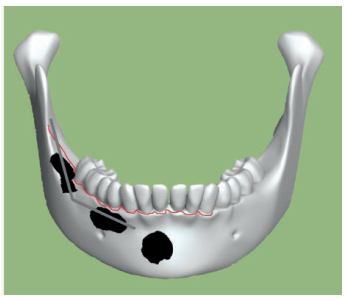

La cirugía se planteó bajo sedación y con el doble objetivo de la eliminación completa de la lesión con el cordal asociado y evitar un debilitamiento excesivo de la mandíbula. Para ello, se realizó un triple acceso a la lesión que nos permitiese por un lado despegar el quiste en toda su extensión mediante el uso de periostotomos y cucharillas de legrado, y por otro lado preservase una serie de “arbotantes” óseos que a su vez permitieran la posterior colocación de una mini placa desde la rama mandibular hasta el cuerpo, que actuase como refuerzo estructural (Figura 4).

A nivel local, se anestesiaron los nervios alveolar inferior y bucal mediante articaina 40mg/ml con 0.01 mg/ml de epinefrina (Ultracain® , España). Se realizó una incisión intrasulcular a espesor total con una descarga distal alta en la rama mandibular que se extendió hasta distal del canino inferior izquierdo sin necesidad de realizar una descarga en este punto. Se despegó el colgajo con la ayuda de un periostotomo para poder acceder a la superficie ósea. Con pieza de mano y fresa redonda de carburo de tugsteno se realizaron tres cavidades equidistantes: la primera a la altura del trígono retromolar (Figura 5), la segunda apical a los premolares inferiores derechos y la tercera mesio-apical al canino inferior derecho. Dichos accesos permitieron abordar y despegar toda la lesión en su extensión para posteriormente poder traccionar de ella a través de la cavidad media (Figuras 6 y 7). La cavidad posterior sirvió también para realizar la exodoncia del cordal (Figura 8). Tras la eliminación del quiste se llevó a cabo un legrado minucioso de la cavidad remanente y se limpió con agua oxigenada. A continuación, se colocó la mini placa con una extensión desde la rama mandibular hasta mesial de la cavidad media. Por último, se reposicionó el colgajo y se suturó de forma hermética mediante una sutura poliamida recubierta no reabsorbible de 4/0 Supramid (Aragó® ) (Figura 9). La muestra obtenida se conservó en formaldehido al 10% y se envió al anatomopatólogo, el cual confirmó el diagnóstico de quiste dentígero sin displasia celular (Figuras 10 y 11).